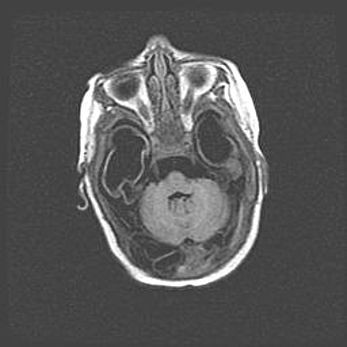

Сообщающаяся гидроцефалия. Кистозная энцефаломаляция головного мозга.

Возраст: 3 месяца 4 дня

Вес: 3100 г

Пол: женский

Окружность головы: 34 см

Срок гестации: 31 неделя

Кистозная энцефаломаляция головного мозга - одна из форм поражения головного мозга в детском возрасте. Характеризуется возникновением множественных и распространённых кист в коре, белом веществе и подкорковых образованиях головного мозга у плодов, новорождённых и детей раннего возраста. Развитие кистозной энцефаломаляции связано с внутриутробной асфиксией и гипотонией, родовой травмой, тромбозом синусов, пороками развития сосудов, инфекциями, сепсисом и другими причинами. Наиболее значимые инфекционные агенты: вирусы простого герпеса, цитомегалии, краснухи, токсоплазмы, энтеробактерии, золотистый стафилококк и другие.